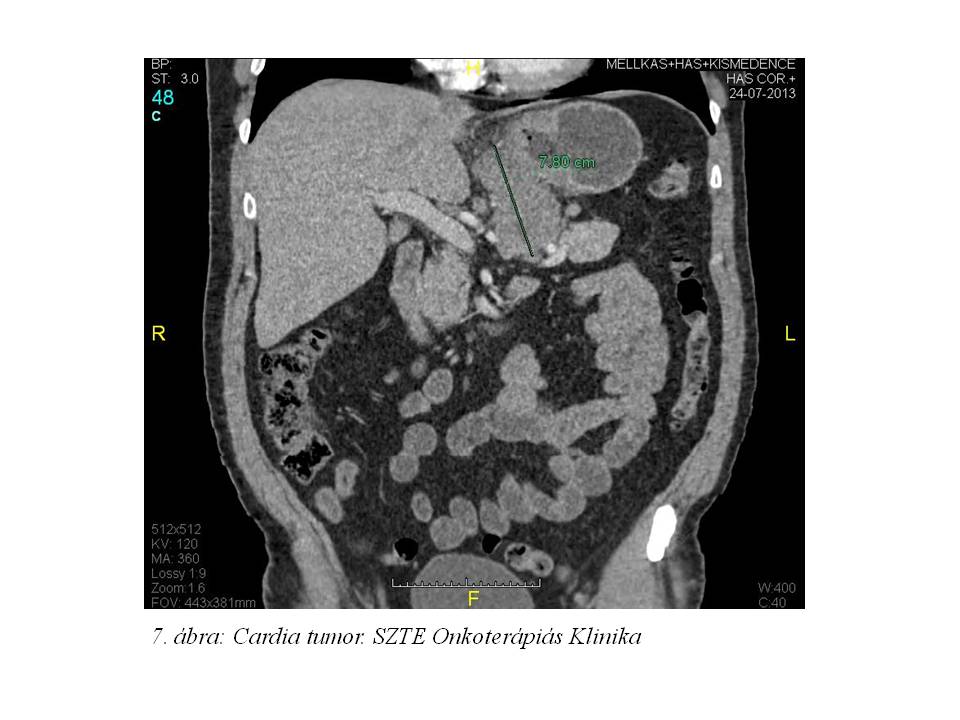

44 éves férfibetegünknél 2013 nyarán fokozódó nyelési panaszok miatt indult kivizsgálása nyelési panaszok és bőrelváltozások miatt. Bőrelváltozásai mindkét oldalon az axillákra, és az inguinakra kiterjedtek, borsnyi, borsónyi veruccosus formában. A bőrgyógyászati diagnózis acantosis nigricans (1. ábra, 2. ábra, 3. ábra, 4. ábra, 5. ábra) lett, mely felvetette paraneoplasiás szindróma lehetőségét. Az elvégzett CT vizsgálat (2013.07.24., 6. ábra, 7. ábra) a gyomor kisgörbülete mellett a fallal összefüggésben a cardiát érintő 43x92x78 mm-es lágyrész képletet írt le, mely a zsírteret infiltrálta, mellette néhány kóros nagyságú nyirokcsomó helyezkedett el. 2013.09.05-én gasztoscopia során biopsiás mintavétel történt, a szövettani feldolgozás adenocarcinomát igazolt (T3-4 N1 M0; adenocarcinoma exulceratum, közepesen differenciált, HER2: negatív). Tumormarkerei a következőek voltak: CEA: 84.57 ng/ml (emelkedett), CA 19-9<0.6 U/mL (normális), CA 72-4: 1.64 U/mL (normális). 2 hónap alatt 25 kg-ot fogyott. A stádiumra való tekintettel az onkoteam neoadjuváns kemoterápia elindítását javasolta a tervezett opus előtt.